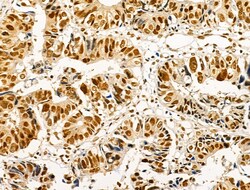

| Immunohistochemistry (Paraffin), Western Blot, Immunocytochemistry | |

| A synthesized peptide derived from human AKT1(Accession P31749), corresponding to amino acid residues around phosphorylated Ser124. | |

| Human, Mouse, Rat | |